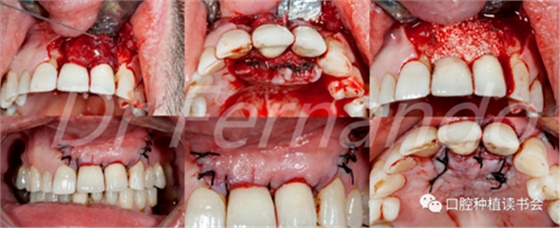

在治療種植體周圍炎方面,唯一有效的治療方法是進(jìn)行外科手術(shù)(圖4 )。然而,手術(shù)治療只是部分有效;Leonhardt等人 描述在5年的時間里,超過一半的種植體周圍炎使用手術(shù)和抗菌治療是有效的。Heitz-Mayfield等 也證明,在短期(1年)內(nèi),用外科翻瓣加抗菌治療能夠有效地阻止90%的種植體周圍炎的發(fā)展;但在這些病例中,仍有50%的患者有探診出血。

圖4 前牙美學(xué)區(qū)種植體周圍炎采用手術(shù)&骨再生治療